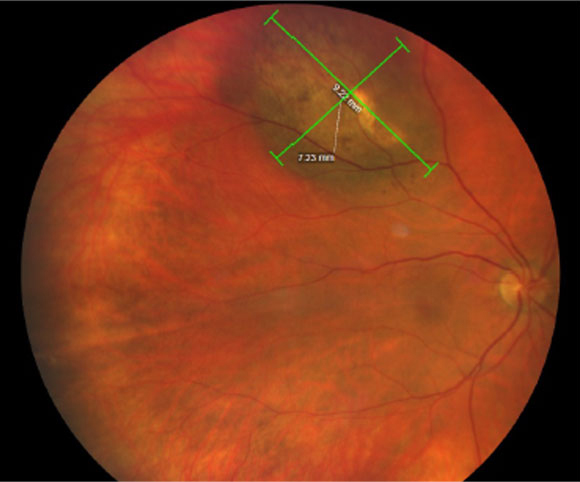

L-Lactate Levels in Aqueous Humor Higher in those with Uveal Melanoma Researchers suggest this could be a promising biomarker to aid in early diagnosis of this highly fatal disease. Read more: reviewofoptometry.com/article/llacta… #optometry #optometrist #eyecare #uvealmelanoma